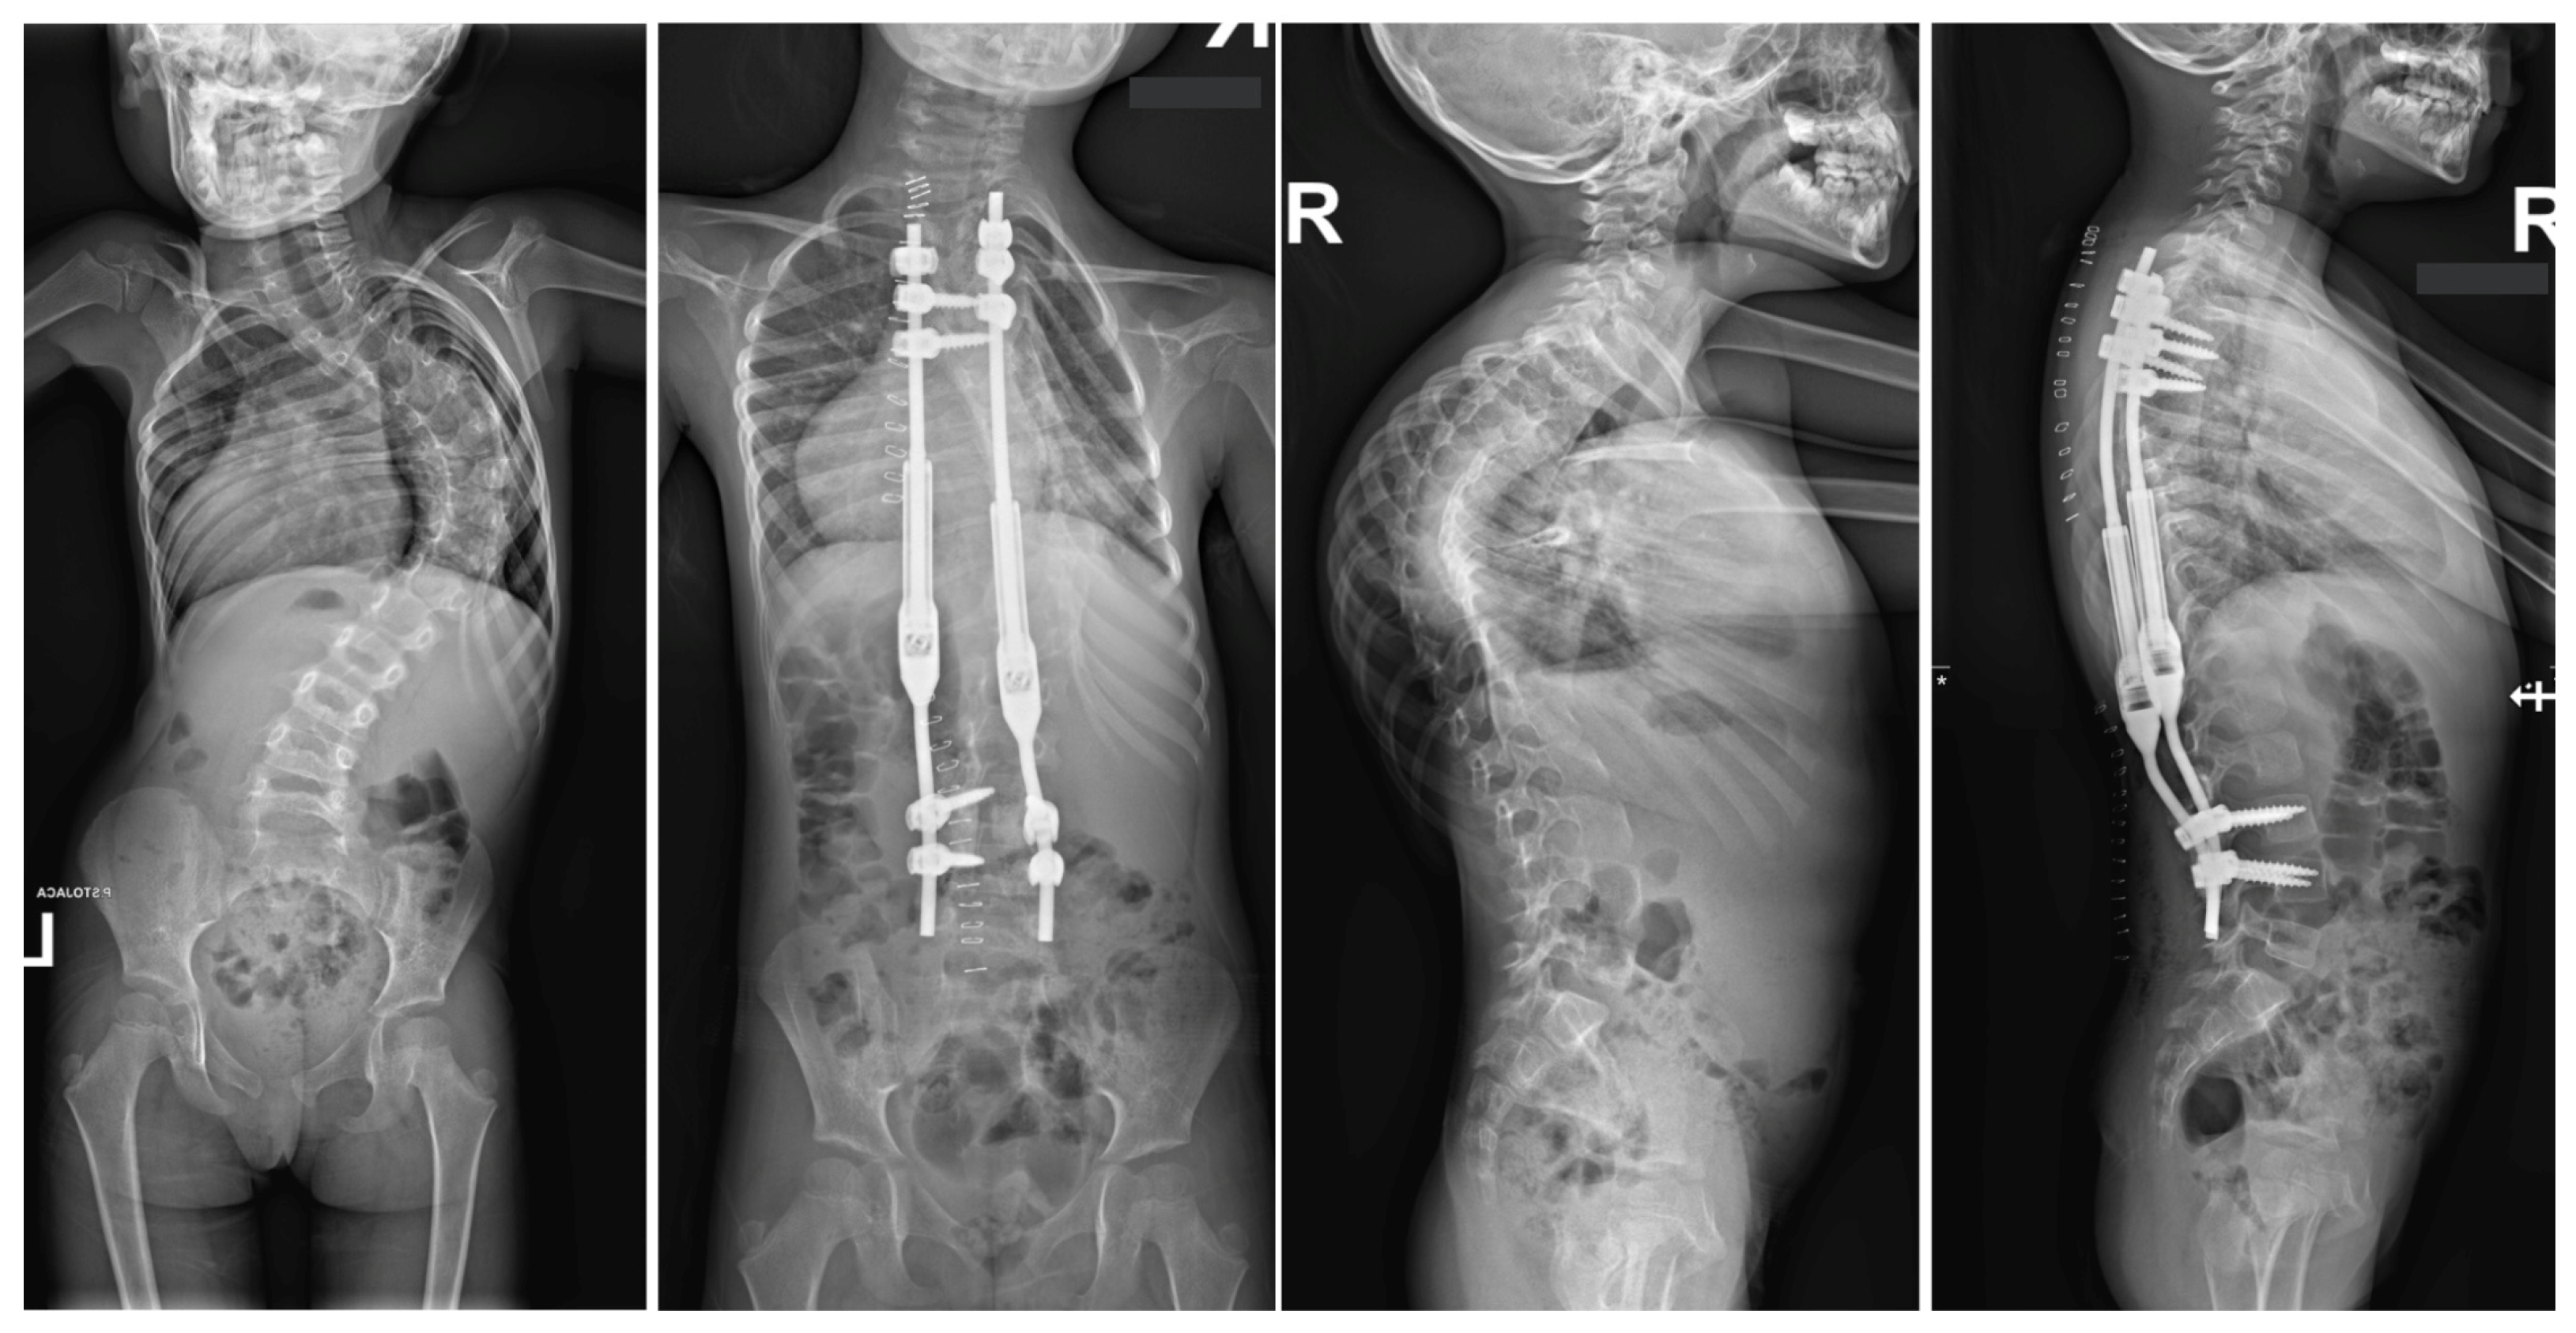

6. Anterior Release

Anterior release procedures are often performed in the thoracic and lumbar spine to aid in increasing flexibility and correcting sagittal and coronal deformities, as mentioned in several studies [51,64]. These procedures, which involve anterior release and fusion, can be executed through either an endoscopic or open approach, with similar outcomes reported in the literature [51,64]. However, severe deformities present challenges due to anatomical changes in the chest wall and spine, making the endoscopic approach impractical in such cases. It is important to note that both the endoscopic and open methodologies have been associated with negative impacts on pulmonary function when compared to the posterior-only approach, a fact supported by various research studies [8,65,66,67]. In the thoracic spine, the surgical process typically includes excision of convex rib heads, removal of discs and posterior annulus, and the release of the posterior longitudinal ligament. Following this, the convex inferior endplate is often removed, sometimes along with the excision of the convex superior endplate, with or without the excision of the convex superior endplate, but the convex superior endplate is excised as well. Moreover, it is common practice to recommend anterior structural reinforcement in the lumbar spine and at the thoracolumbar junction to help prevent the development of kyphosis. After undergoing anterior release and fusion procedures, patients with severe and rigid curves may require instrumentation both anteriorly and posteriorly to enable a safe and effective three-dimensional correction of the spinal deformity [8,67]. The utilization of total pedicular constructs, with enhanced segmental fixation and improved capacity for tridimensional correction of AIS curves, has reduced the necessity for an anterior approach in specific curves. The anterior release technique encompasses the elimination of discs and rib heads near the apex of the curve, thereby enhancing spinal flexibility [8,66,67]. This procedure not only augments curve flexibility, but also ameliorates thoracic kyphosis during the subsequent posterior fusion. These adjustments are imperative for achieving appropriate post-operative spinal alignment in both sagittal and coronal planes. Following anterior release, patients typically undergo a secondary posterior spinal fusion to rectify scoliosis, which can be performed either in a single stage or in a staged manner [55,68]. Studies have reported that this combined approach achieves a correction rate of 40–50% in individuals with severe scoliosis [4,50,68,69,70]. Helenius et al. have asserted that at present, the primary indication for the anterior release technique is Lenke 5C thoracolumbar or lumbar adolescent idiopathic scoliosis curve, typically spanning levels T11 to L3 [71]. Controversy arises when comparing anterior–posterior release with other surgical methods, such as posterior-only release and anterior–posterior vertebral column resection, for the management of severe adult scoliosis. The principal benefits of combined anterior–posterior release encompass three-dimensional curve correction in severe and rigid idiopathic cases, reduced neuromuscular complications, infections, and pseudarthrosis [4]. Ren et al. discovered that anterior–posterior release is more effective than anterior–posterior vertebral column resection [49]. Some of the complications linked with anterior release include pseudoarthrosis and pulmonary issues [71]. Figure 5 shows X-rays of a 11-year-old girl treated with an anterior release, followed by the placement of magnetically controlled growing, and when she turned 11, she underwent a procedure involving conversion to posterior spinal fusion, replacement of MCGRs, and multi-level posterior release with Ponte osteotomy.

Figure 5.

Radiographs revealed an 11-year-old female with severe early onset idiopathic scoliosis and asymptomatic spondylolisthesis. At the age of four, she underwent a four-level anterior release using a mini-open anterior approach, followed by the placement of magnetically controlled growing rods (MCGRs) through a less-invasive technique and subsequent periodic ambulatory lengthening. When she turned 11, she underwent a procedure involving conversion to posterior spinal fusion, replacement of MCGRs, and multi-level posterior release with Ponte osteotomy.